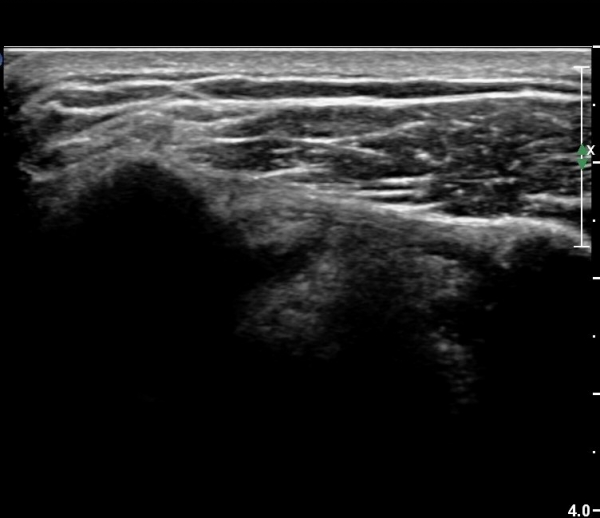

ȸÀü±Ù°³°£°Ý(rotator cuff interval) Ⱦ´Ü¸é°Ë»ç¿¡¼­ °ß°©ÇϱٰǻóºÎ¿Í ±Ø»ó°Ç ³»ÃøºÎ¿¡

ƯÀÌ ¼Ò°ßÀ» º¸ÀÌÁö ¾Ê´Â´Ù(»çÁø 1, 2).